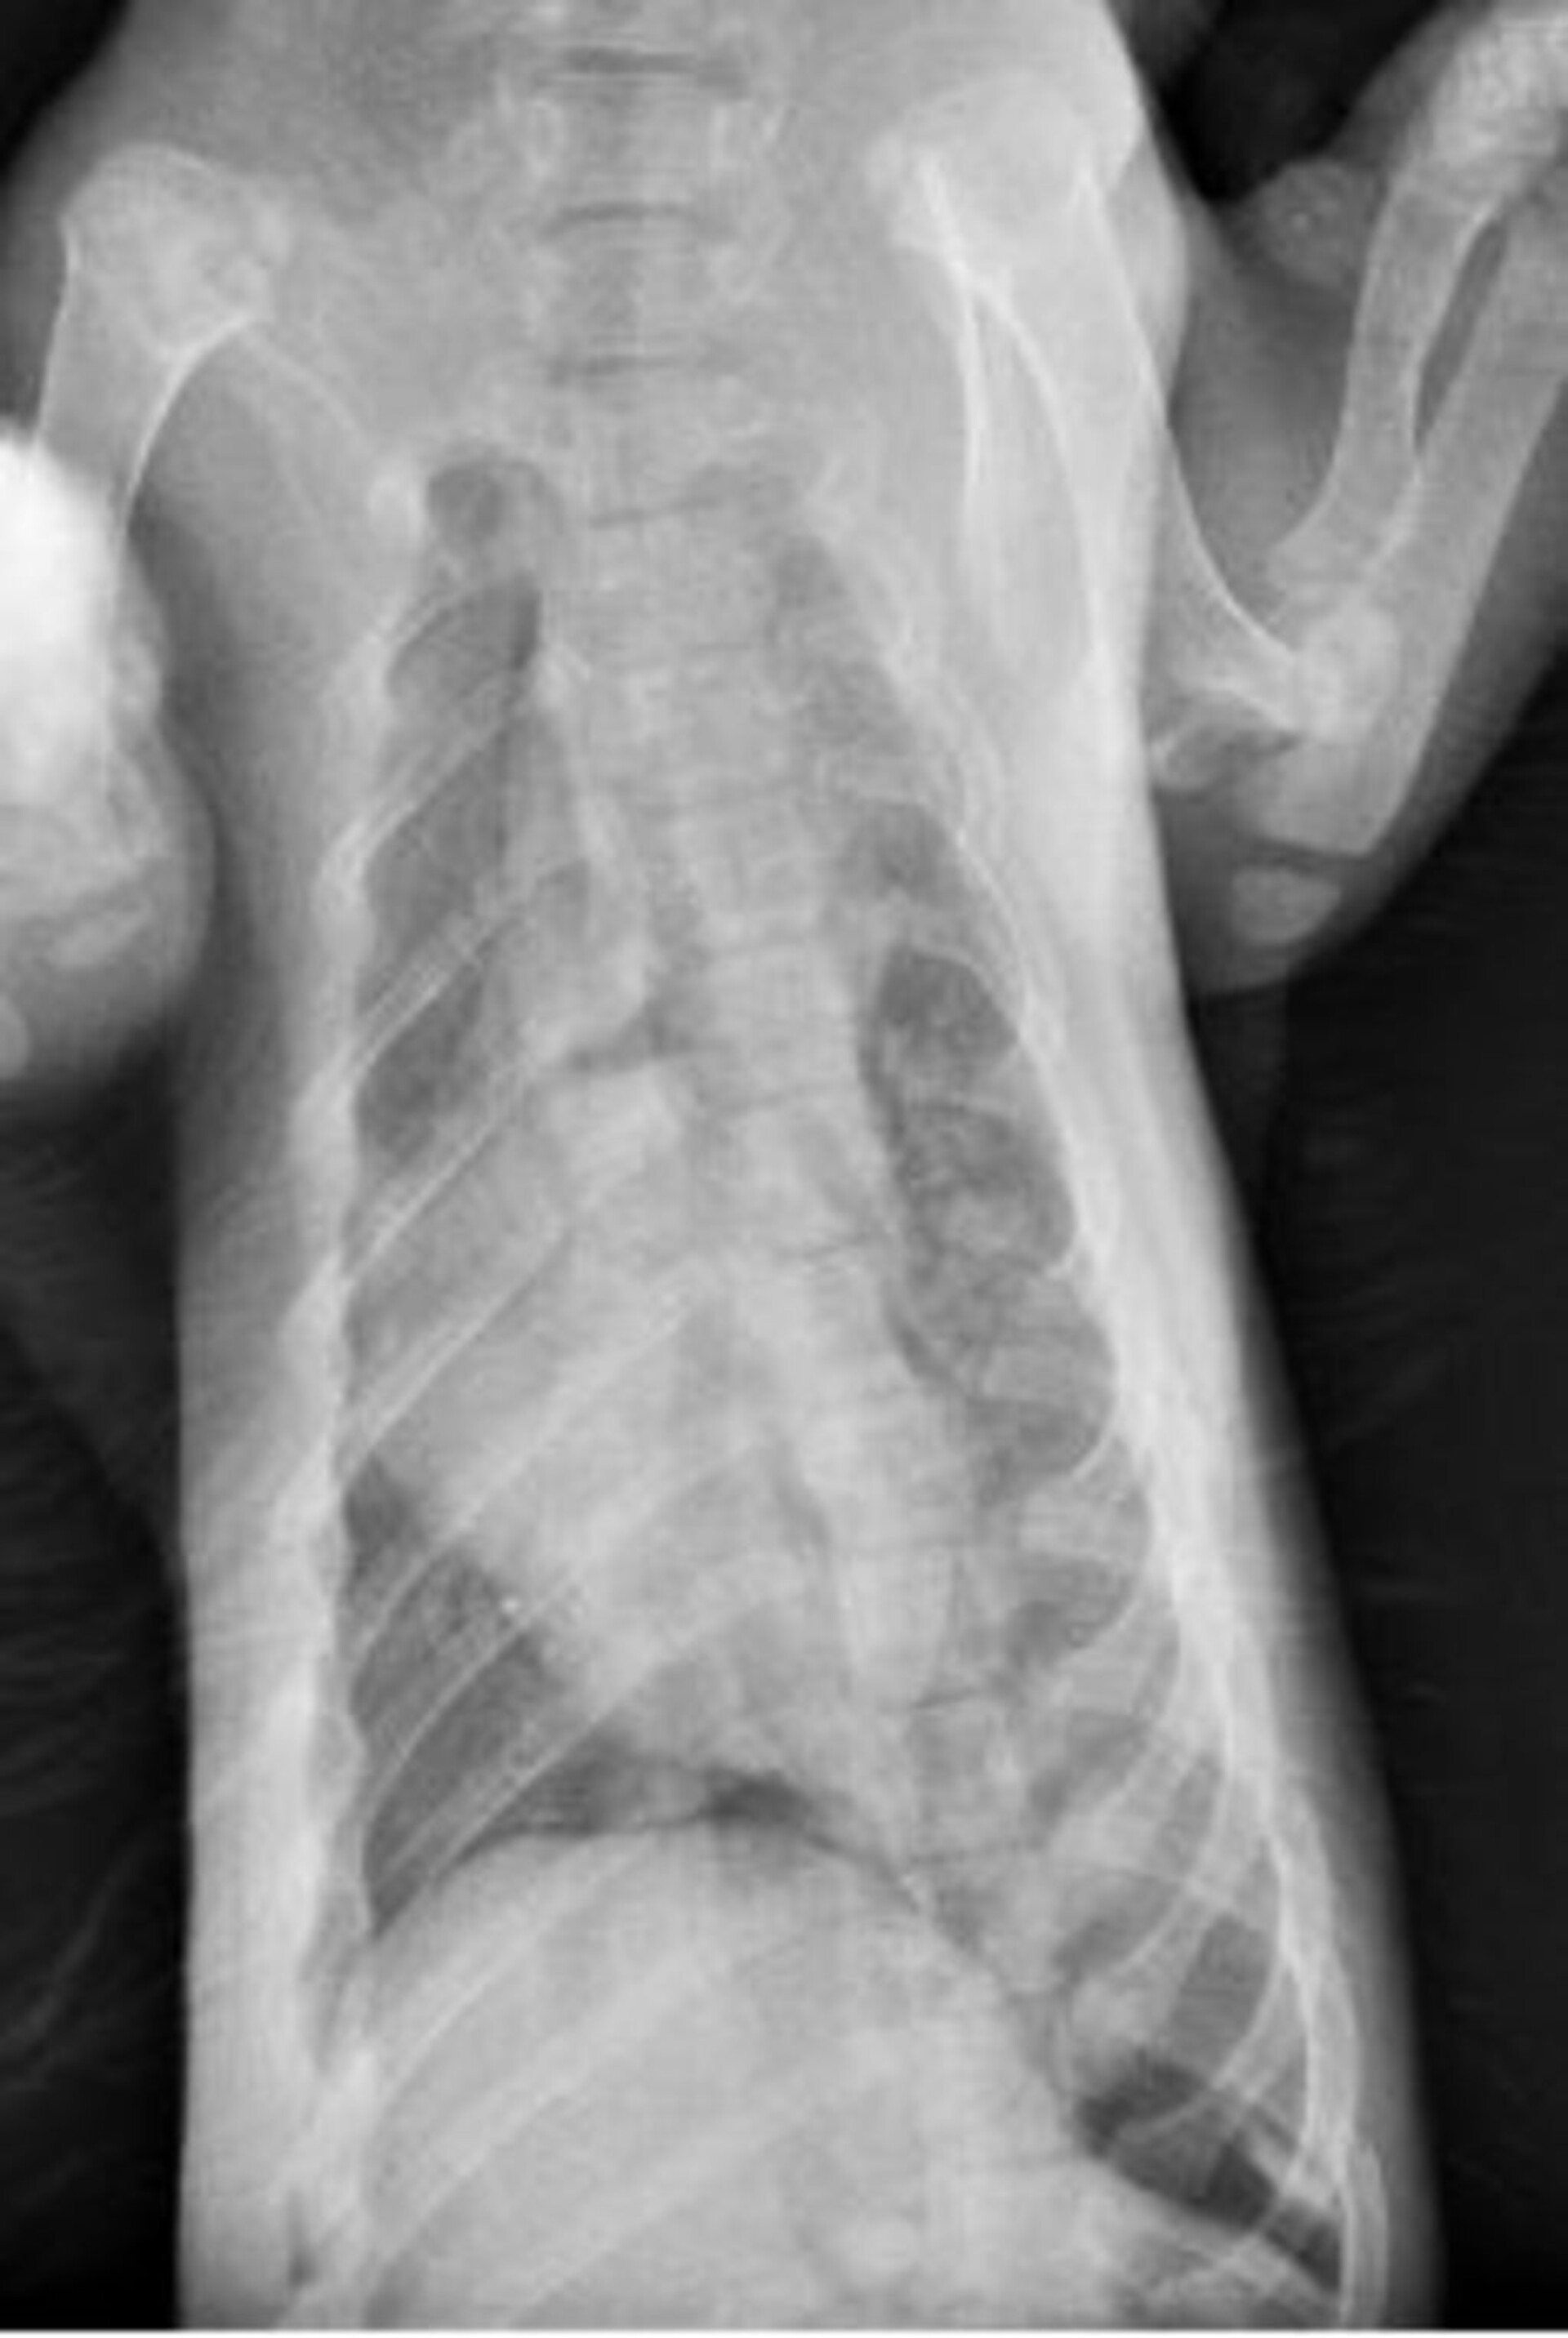

牙齒尚未換成恆久齒。全身長64cm、未含尾長40 cm、胸20 cm、前腳長10cm、後腳長9cm。外表無明顯外傷,頭顱變形,口腔、鼻腔內有血液。

頭骨骨折、下顎骨折、多處肋骨骨折、氣胸。